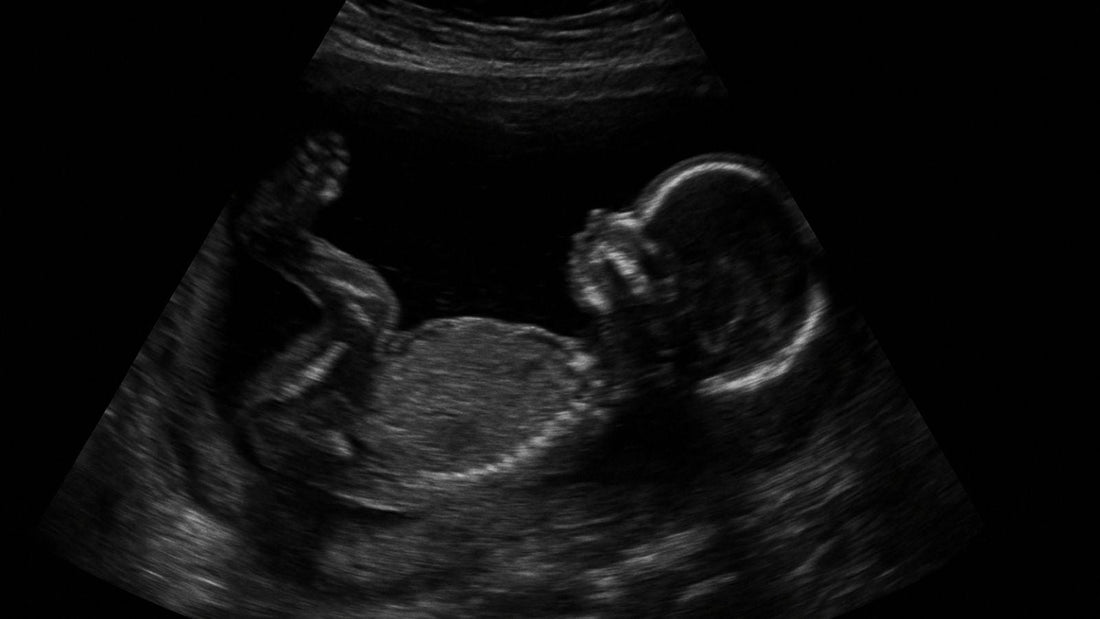

Bébé transverse à l’échographie ? Cette découverte inquiétante est plus fréquente qu’on ne le pense, touchant environ 1 % des grossesses à terme. Rassurez-vous : des solutions existent pour favoriser son retournement ou préparer son accouchement en toute sécurité. Explorez les manœuvres douces, comme les postures adaptées (le pont indien, le décubitus latéral) ou la moxibustion, la version externe guidée par un professionnel, ou une césarienne programmée si nécessaire. Votre équipe médicale sera votre alliée, et chaque étape peut être traversée avec bienveillance, en harmonie avec les valeurs du Monde des Marmottes. Parce que la naissance de votre marmotte mérite d’être sereine, qu’importe le chemin emprunté.

Un bébé en position transverse se tient horizontalement dans l’utérus, comme posé sur le côté. Rassurez-vous : cela concerne environ 1 % des grossesses à terme, et de nombreux bébés se retournent spontanément avant l’accouchement. Cette configuration peut parfois être liée à une anomalie utérine, un excès de liquide amniotique ou une grossesse multiple, mais souvent, la cause reste mystérieuse. Cet article explore les options disponibles, des manœuvres externes à la césarienne, en passant par des méthodes douces. Nous vous guiderons avec bienveillance, en mettant l’accent sur l’accompagnement médical indispensable.

Lorsque bébé adopte une position transverse, il repose horizontalement dans l'utérus, comme bercé dans un hamac. Sa tête se trouve d'un côté, ses pieds de l'autre, sans être aligné avec le col de l'utérus. Cette configuration, aussi appelée présentation de l'épaule, empêche une naissance naturelle. Chères mamans, sachez que cette situation, bien que surprenante, reste une possibilité parmi d'autres durant la grossesse. Concrètement, aucune partie du corps de bébé ne s'oriente vers le canal de naissance, ce qui rend la voie basse impossible.

Le repère médical principal est l’échographie, qui confirme avec précision la position de votre bébé. En pratique, on observe si son axe longitudinal forme un angle de 90° par rapport à votre colonne verticale. C’est souvent en ressentant des coups de pied d’un côté et la tête de l’autre que vous pouvez deviner cette position. Votre sage-femme peut aussi le suspecter lors d’un examen manuel. Mais seul un bilan échographique permet de l’attester formellement. Rien de dramatique : cela permet juste d’ajuster votre suivi pour que tout se passe en toute sécurité.